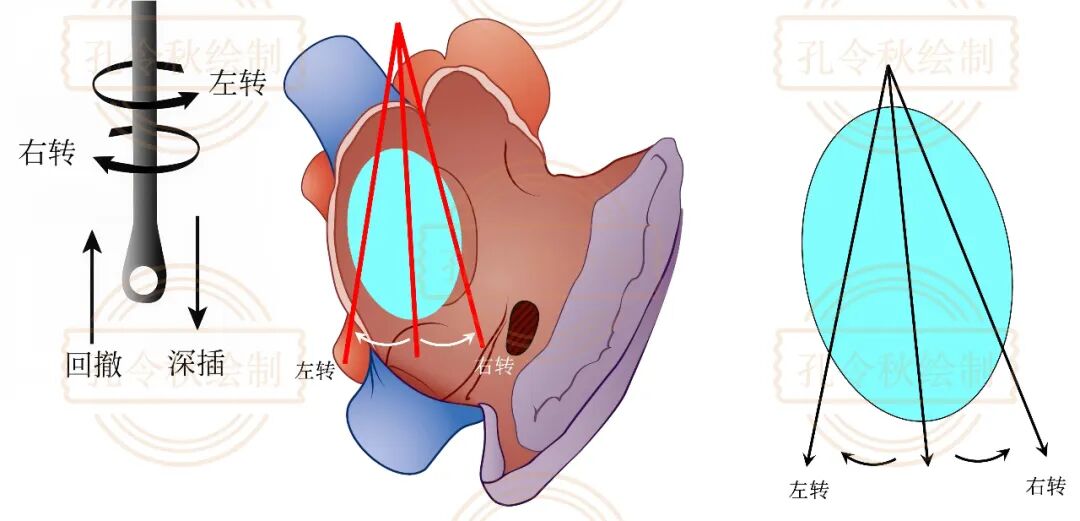

在进行检查过程中,除注意切面不同切面外,即使选择同一个切面,还需要探头深度与角度变化对测量的影响,以免因操作不当漏诊。

下图展示的是探头在食管中的深度变化对切面的影响,当探头深插或回撤时,其切面经过的ASD部位并不相同。

同理,在同一个切面中,通过旋转探头方向,也可以经过ASD不同位置,见下图。个人因为,若仅仅通过二维超声进行测量,应尽量选择测值最大的径线作为参考。